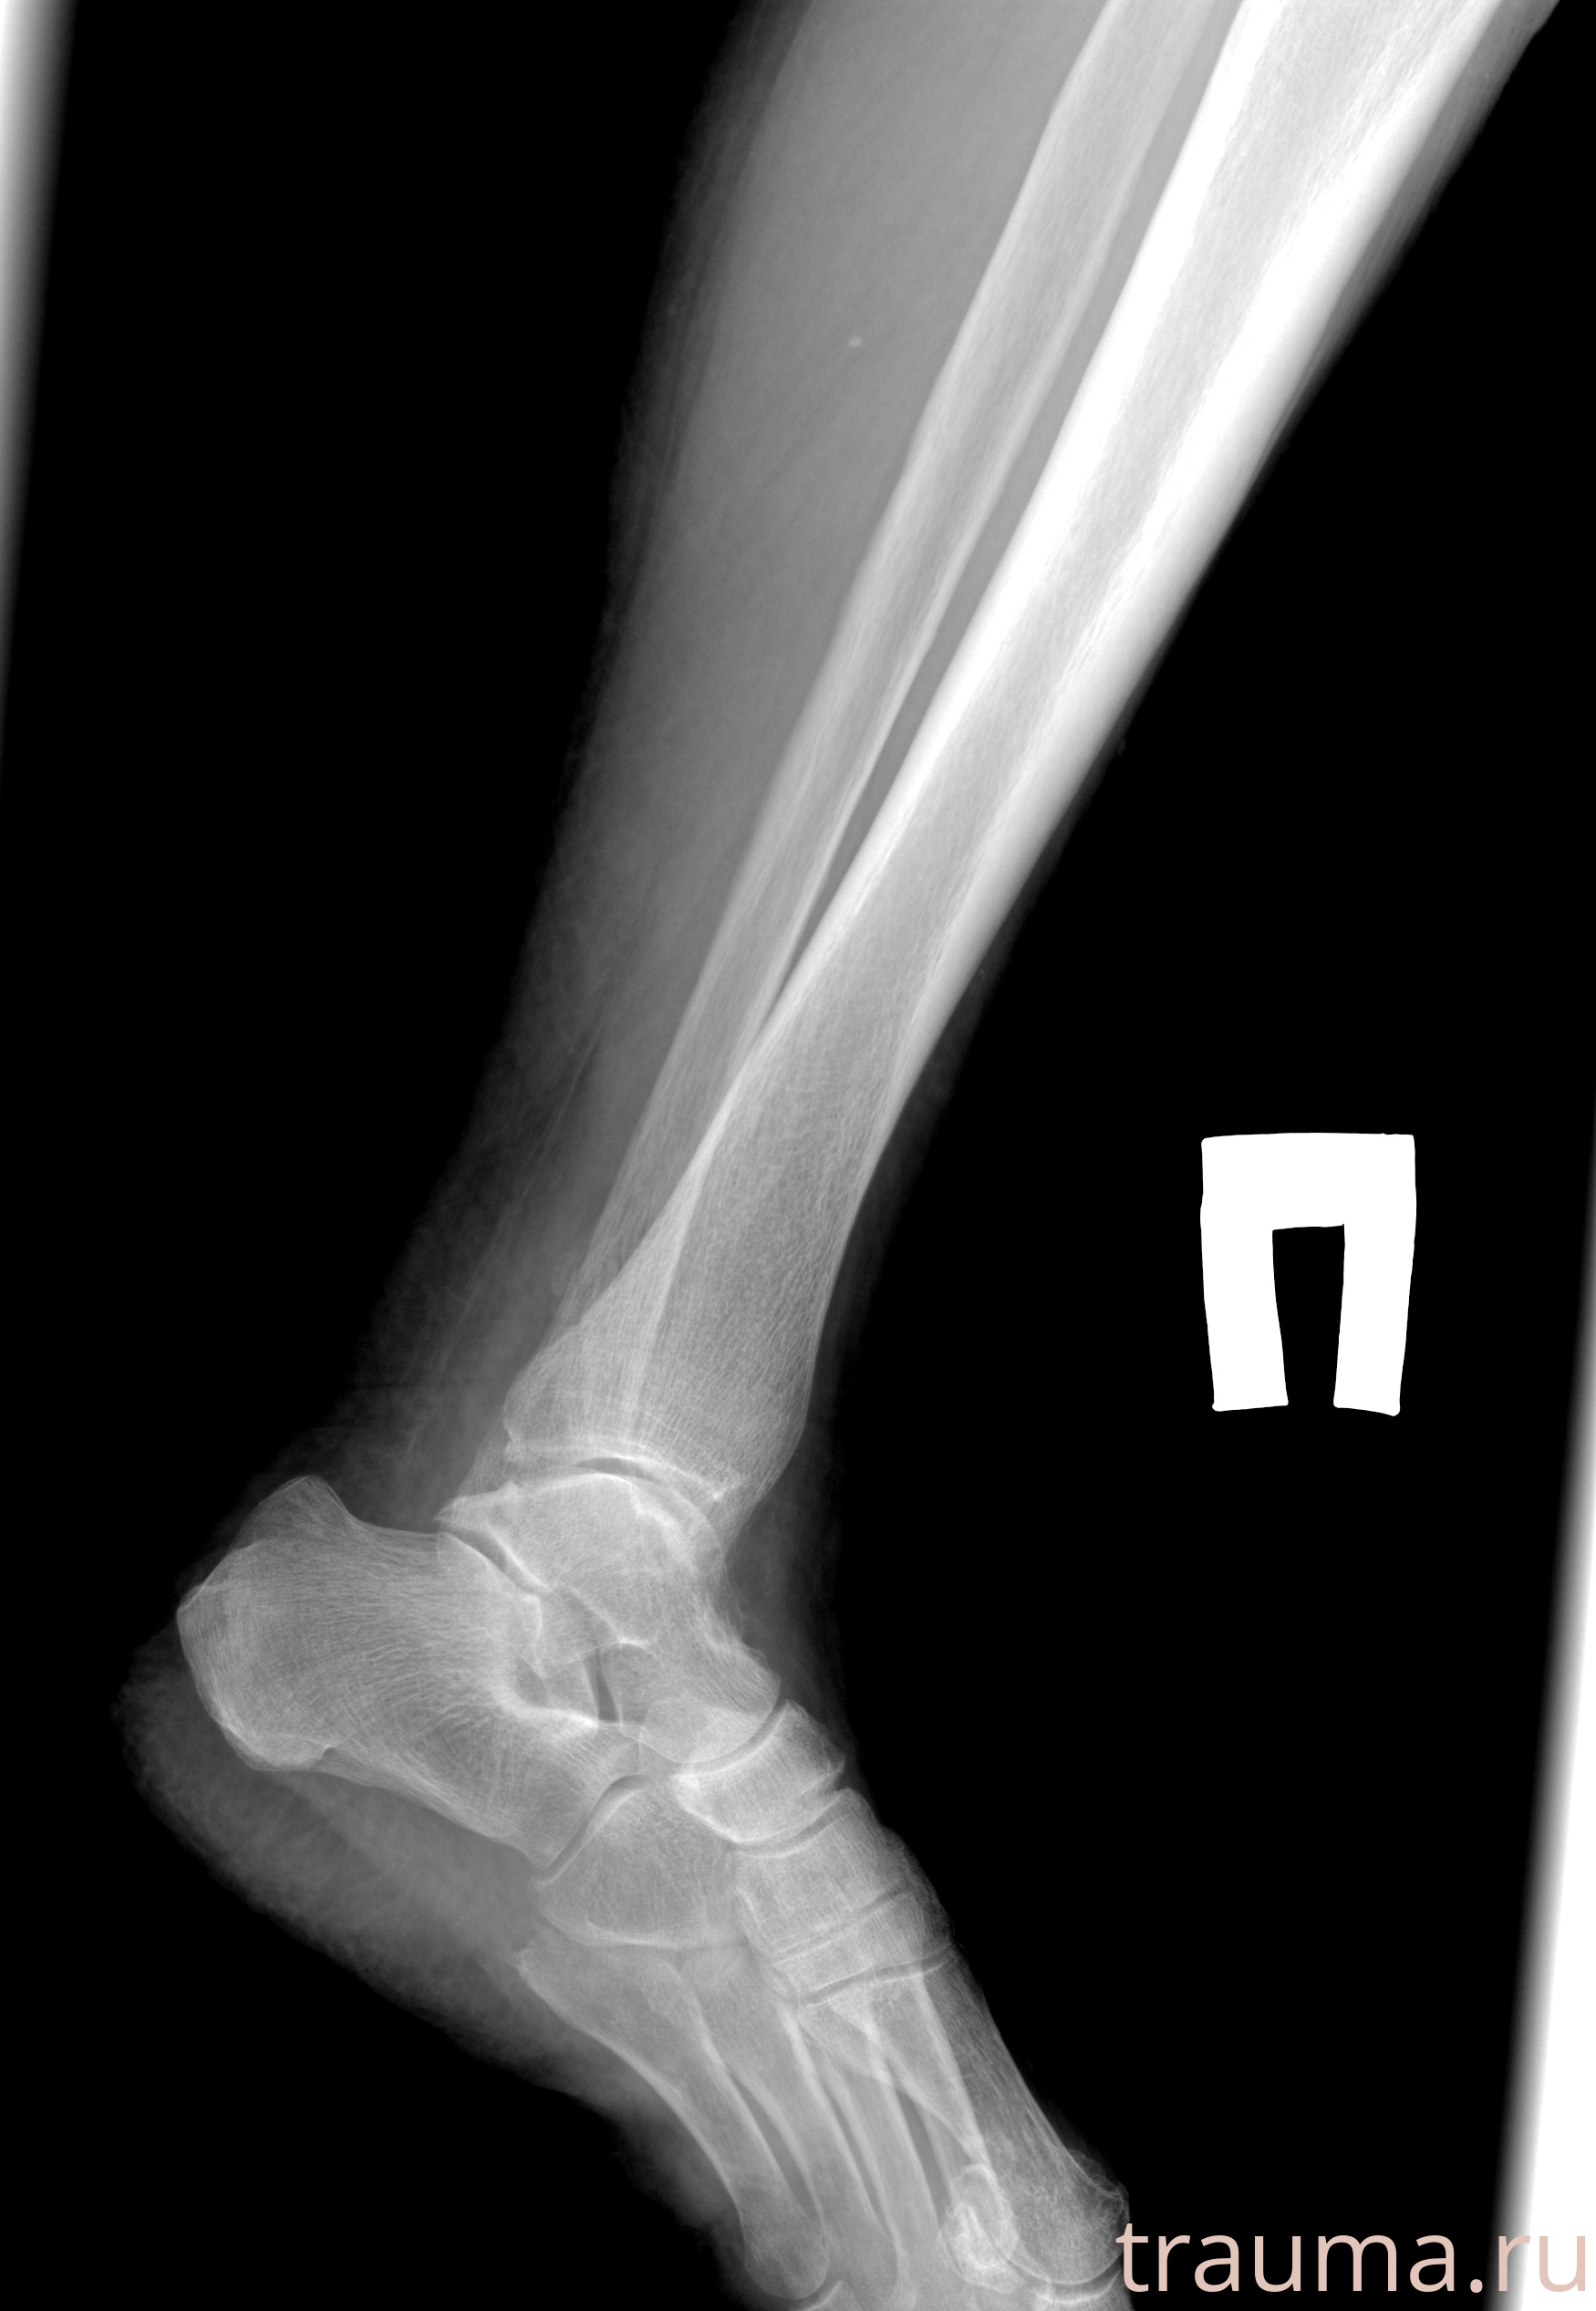

Рентгенограммы

Рентген на дому: по вашему адресу приезжает врач-рентгенолог, травматолог-ортопед с мобильным рентгеновским аппаратом, проводит диагностику травмы или заболевания, делает необходимые рентгенограммы, дает рекомендации по дальнейшему лечению. Получить качественные снимки в домашних условиях возможно благодаря уникальной методике, разработанной МосРентген Центром для института  Склифосовского